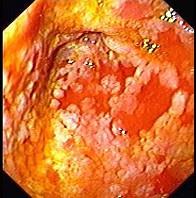

男性,67岁,反复上腹饱胀不适2年,以餐后为甚,伴反酸、嗳气、食欲不振、恶心、呕吐等。胃镜检查胃窦粘膜见散在灰白色斑块,如图:该病人最可能的诊断是 ( )...

问题 男性,67岁,反复上腹饱胀不适2年,以餐后为甚,伴反酸、嗳气、食欲不振、恶心、呕吐等。胃镜检查胃窦粘膜见散在灰白色斑块,如图:该病人最可能的诊断是 ( )

选项 A.胃黄斑瘤 B.慢性浅表性胃炎 C.慢性萎缩性胃炎伴肠上皮化生 D.胃泌素瘤 E.消化性溃疡

答案 C